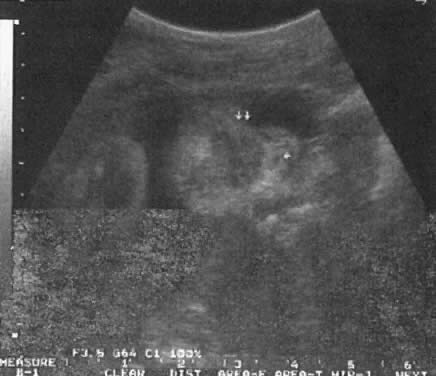

The Ureteropelvic Junction

Dilation of the UPJ (Fig. 14) results from (1) abnormal recanalization of the upper part of the ureter, resulting in varying degrees of obstruction; or (2) absence of the longitudinal muscle fibers in the upper ureter and renal pelvis. In the latter dysfunction, there is abnormal forward propulsion of urine, resulting in a dilation of the UPJ.46 Importantly, dilation of the UPJ may be associated with other anomalies involving the fetal cardiac, gastrointestinal, and central nervous systems.

Fig. 14. A. Cross-section of fetal abdomen at level of kidneys ( spine anterior ) show both kidneys. The left (LT) kidney shows dilation of the ureteropelvic junction (UPJ), but no hydronephrosis is present. B. The fetal spine is tot he left of the echogram and the kidney above the spine also shows dilation of the UPJ, the anteroposterior diameter (calipers) measuring 8 mm. C. The fetal spine is on the right lower side of the echogram. The kidney above the spine shows more severe UPJ (calipers) , with extension to the calyces.